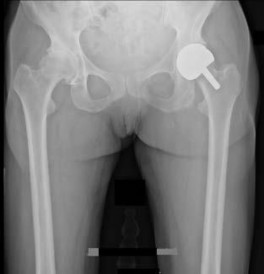

is the anteroposterior hip radiograph of a 74-year-old healthy and active man who was seen in the office 18 months after a primary uncemented total hip replacement with a history of 3 hip dislocations.The last dislocation occurred 1 week ago and he was treated in the emergency department with a closed reduction and application of a hip abduction brace.

---

All episodes of dislocation occurred when bending forward. Aside from the episodes of dislocation, his hip functions well. Examination revealed a normal gait with good abductor strength and pain-free hip movement. What is the most appropriate next treatment step?

Explanation

This patient has had 3 hip dislocations since his hip replacement, and the radiograph shows an underanteverted cup. He will likely continue to dislocate and surgery is indicated. The anteroposterior radiograph indicates that the cup is vertically oriented and not anteverted. His acetabular component is malpositioned and should be revised to provide the highest likelihood for success. A simple head and liner exchange with a malpositioned implant is less

likely to succeed. Additionally, the radiograph shows sufficient acetabular bone stock medial to the cup. The addition of acetabular revision caries a low risk for increased morbidity and will allow a large cup with a larger femoral head with sufficient polyethylene thickness. PREFERRED RESPONSE: 2